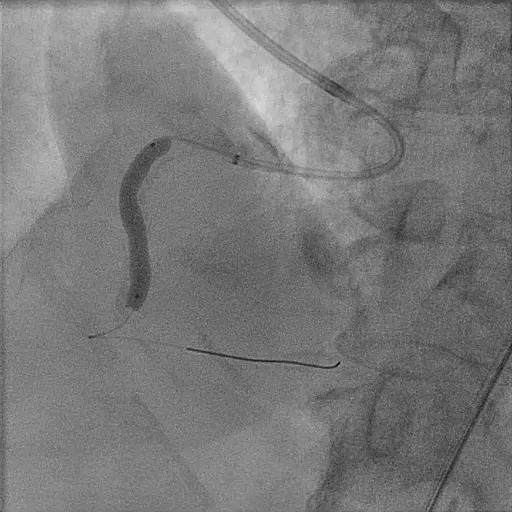

Radial approach. AL guided 6.5 3.5F. Runthrough wire down to distal RCA. predilate 2.5x15mm wire cannot pass stenotic lesion.

Change tp 1.5x15mm ballon to rate burst. Unable to cross IVUS catheter in. Predilate 2.5x15mm wire high pressure. Proceed with Lithix ballon 3.5x14mm preparation from distal to proximal RCA , multiple time ( distal 8atm x 3 , proximal 10-12 atm multiple slow inflation. Post Lithix , angiogram show good TIMI3 flow, mild linear dissection noted , good preparation. We proceed with 1xDCB over distal RCA and 1x DCB over midRCA 4.0X30 at 9atm. Post DCB noted recoil over distal RCA , then proceed with 1XDES 4.0x34 at 12atm at distal RCA. prox RCA treated with 1x DES till ostial RCA 4.0X34mm at 12atm. IVUS run post PCI , good stent expansion and opposition. Angiogram Post stent good TIMI 3 flow , no recoiled , accepted linear dissection . Patient well post PCI discharge well the next day.